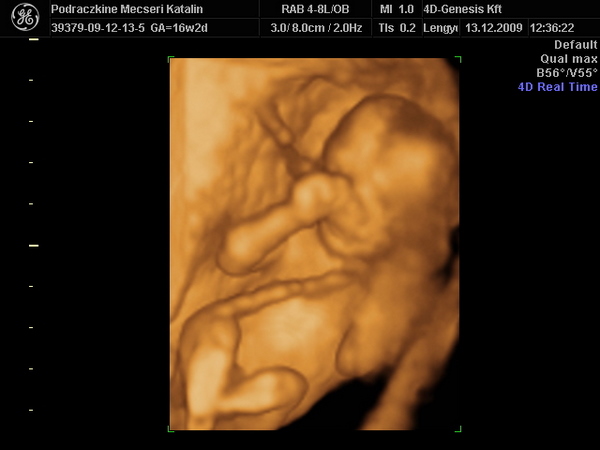

Újabb pasi érkezik Kolos. :D

16 hetesen ilyen. :wink: